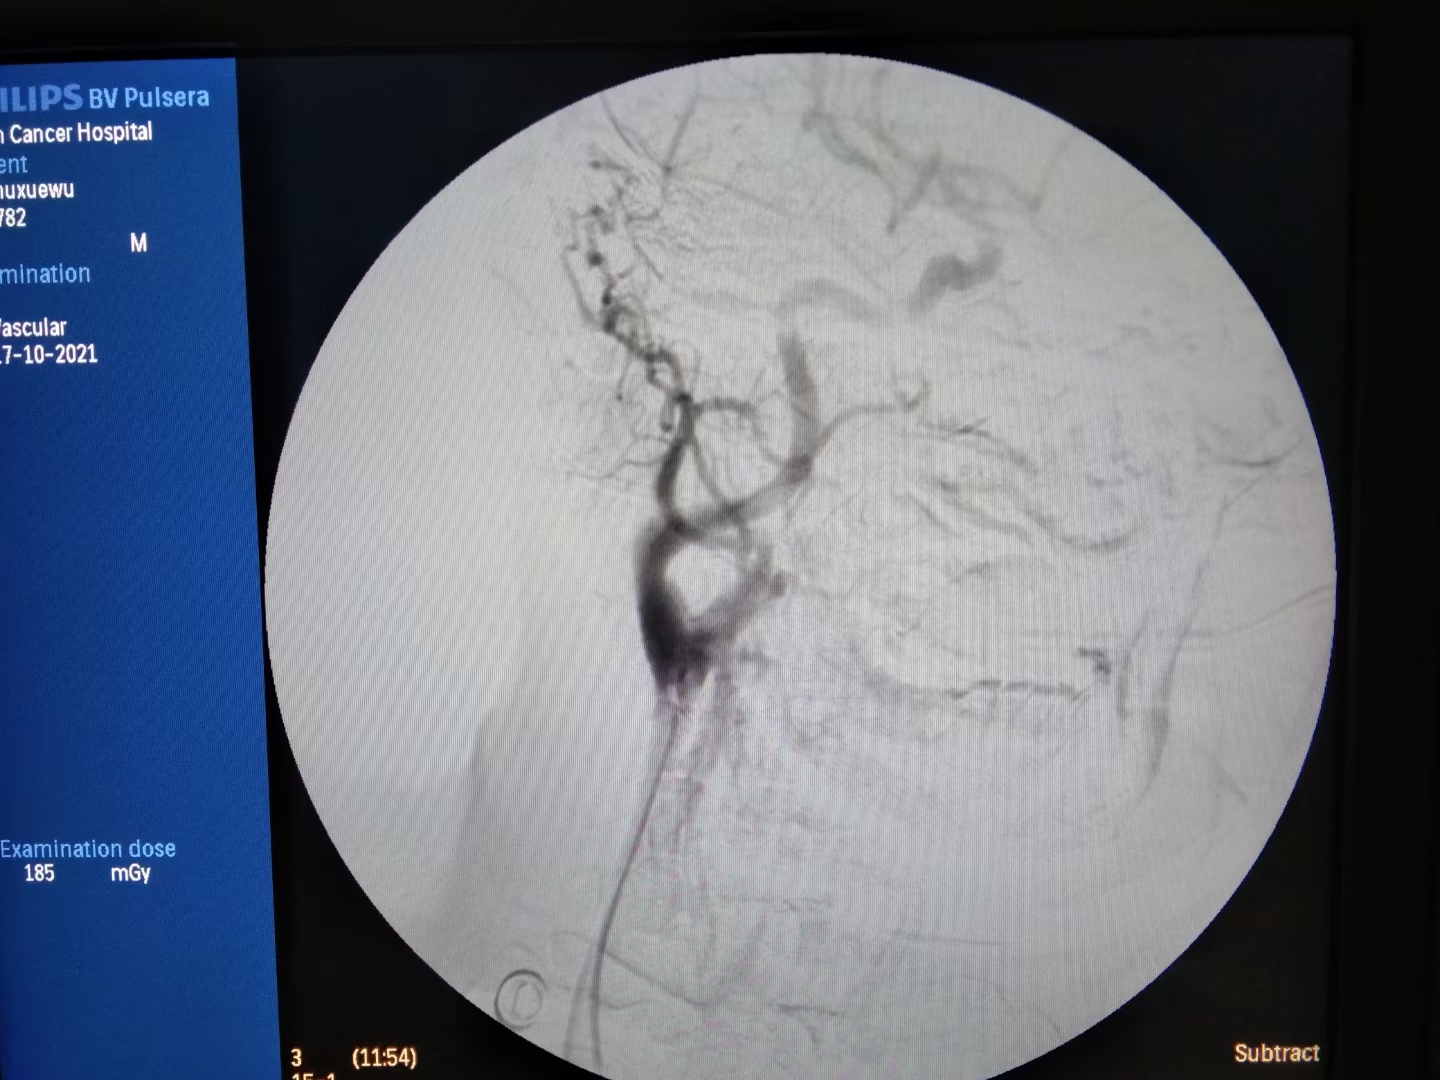

分享一个病例,舌癌患者放化疗后突发大出血,出血约1000ml。

边扩容,输血,止血的同时,推入介入室。消毒、铺巾、穿刺、插管,造影。

术中患者燥动,带来极大风险,一旦误栓颅内动脉,将是灾难性后果。

最终,颗粒+弹簧圈完美栓塞。出血停止,患者生命体征平稳。